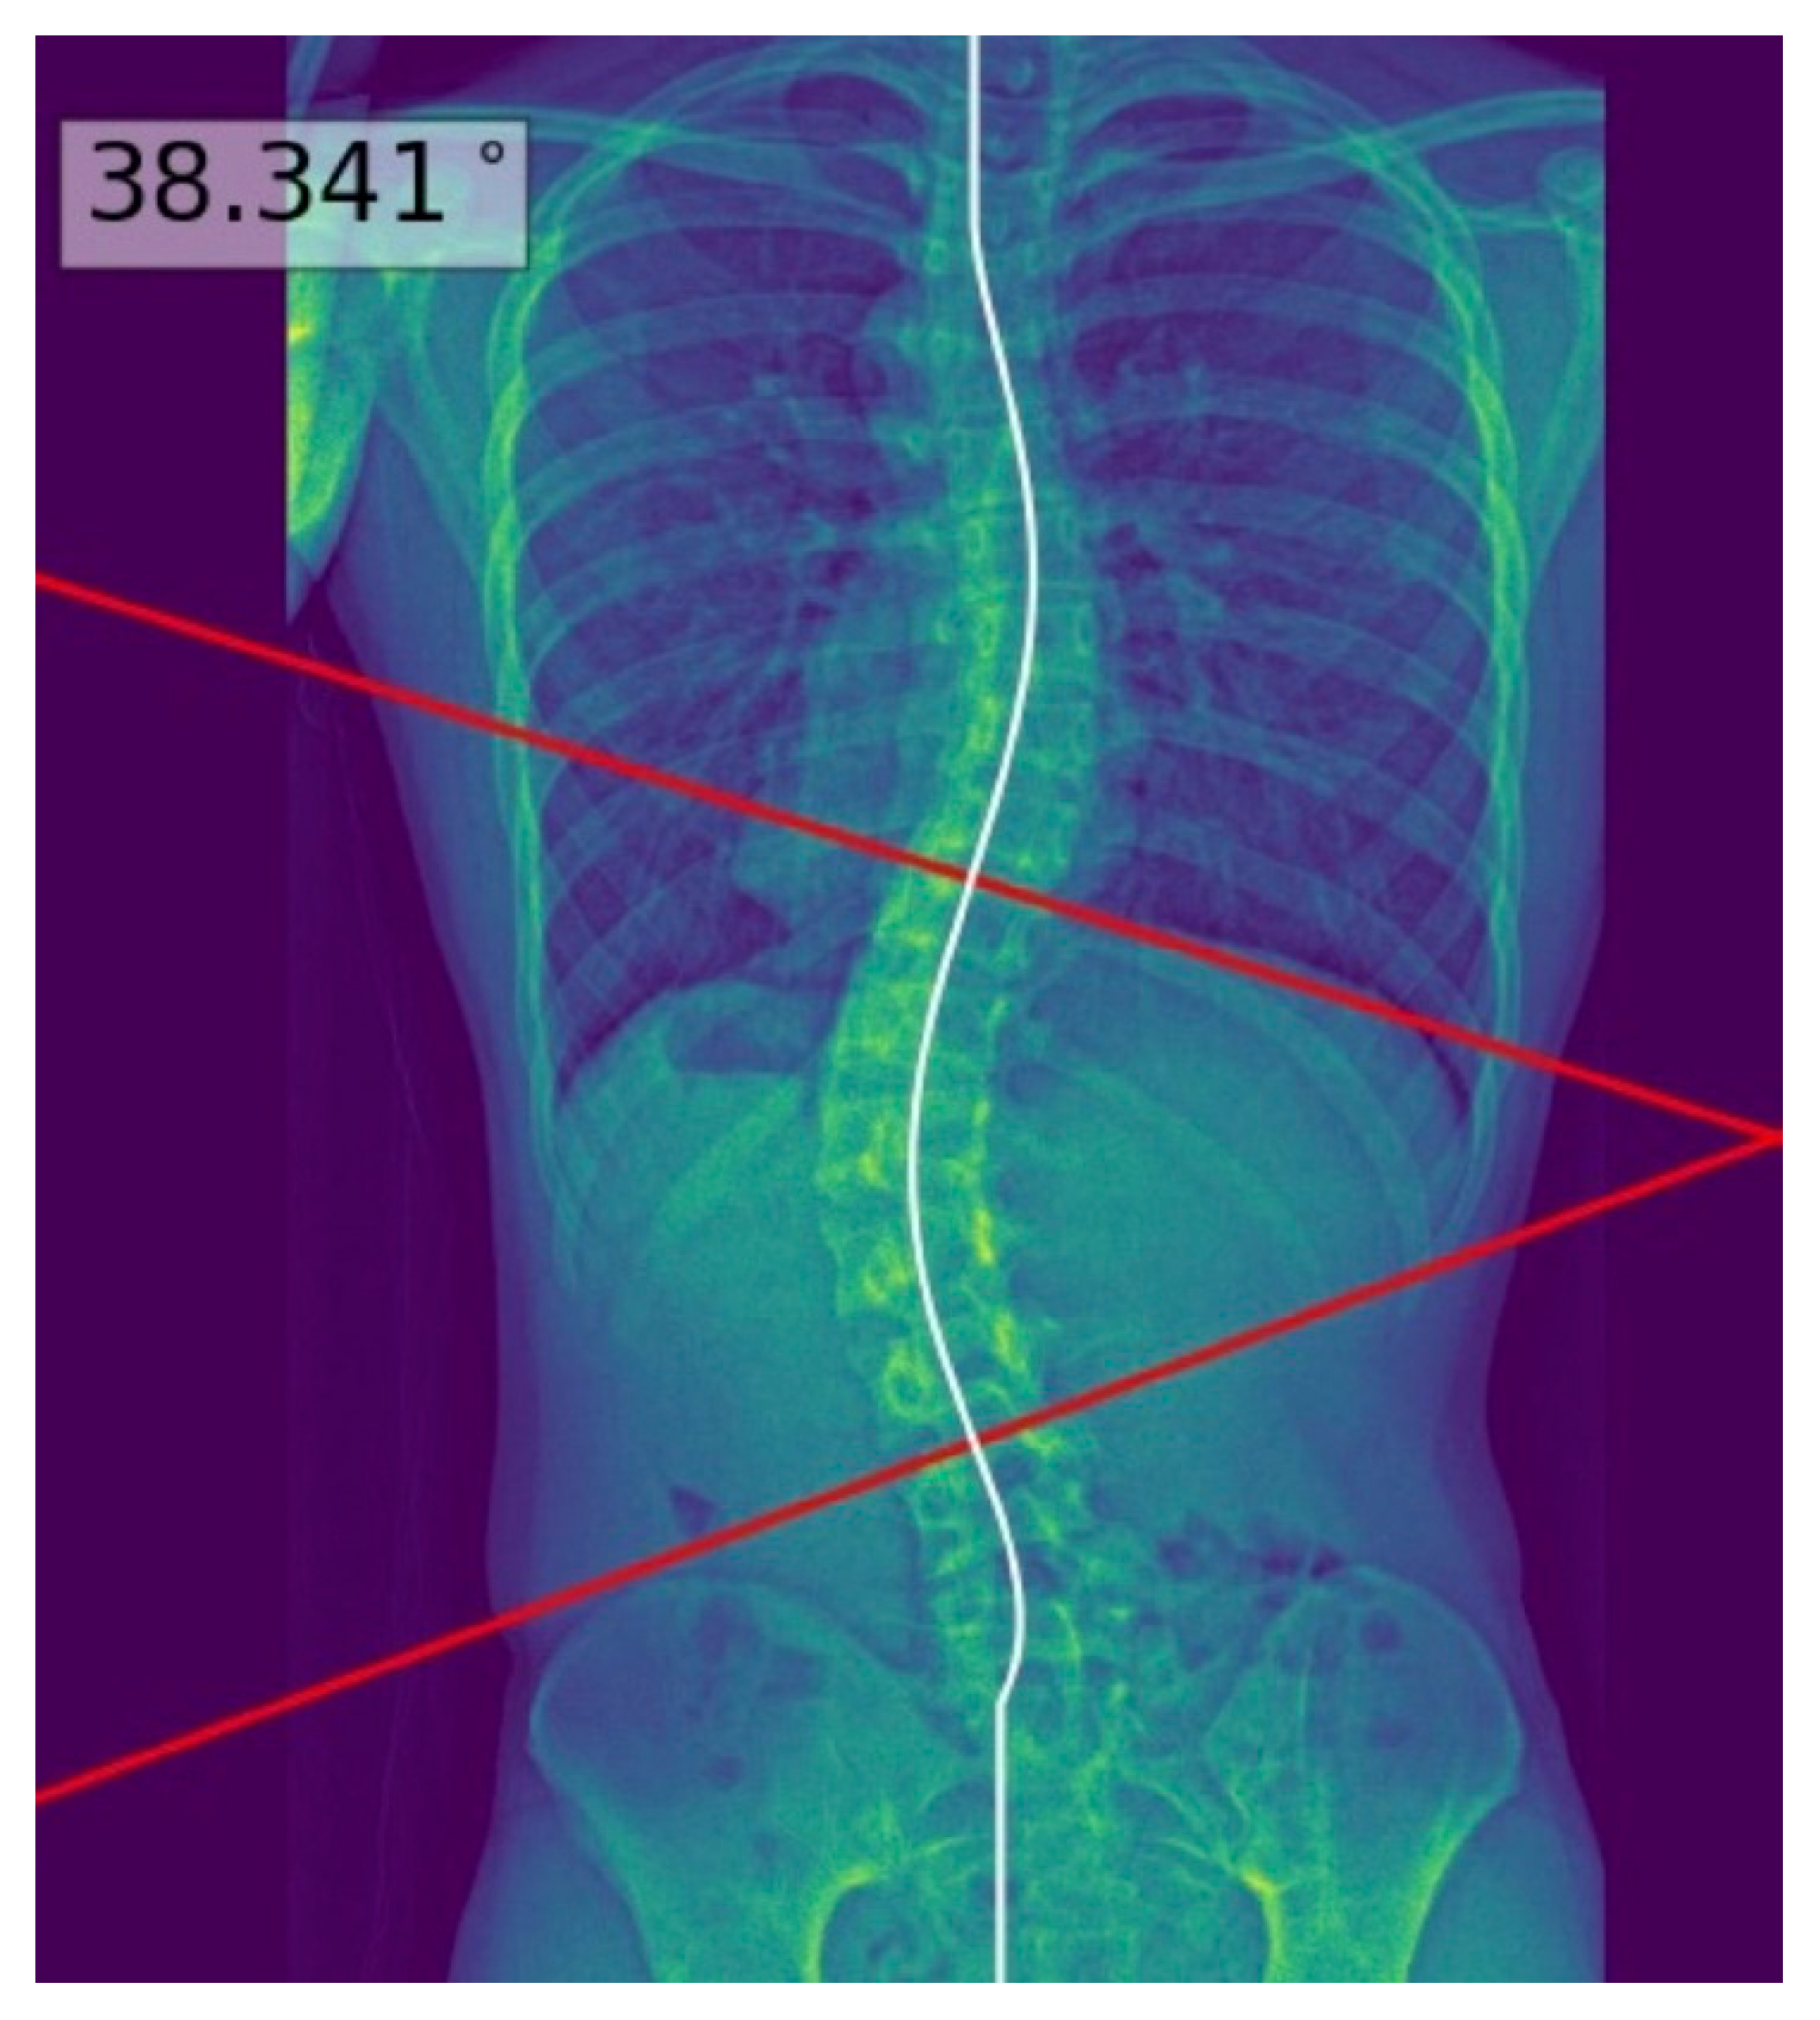

Radiographic evaluation of suspected scoliosis is crucial for diagnosis and further management [5]. On a standing posteroanterior spinal radiograph, scoliosis is defined as a coronal curvature with a Cobb’s angle of 10 degrees or greater [6]. Figure 1 illustrates an example of the measurement of Cobb’s angle, which refers to the greatest angle between two lines passing through the superior and inferior endplates of two appropriately selected vertebrae. The severity of AIS is classified according to the angle of the major coronal curve, with curves of approximately 10–24°, 25–40° and >40° representing mild, moderate and severe scoliosis, respectively [7,8]. This classification is essential for prognostication and treatment planning [9,10].

The process above allowed deep learning model masks of the whole spine (showing individual vertebrae) to be obtained and compared to the manual annotations. The model achieved a Dice similarity coefficient of 0.88 and Intersection over Union (IOU) of 84% on validation; it achieved a Dice coefficient of 0.619 and IOU of 72% on testing. Using the masks, the deep learning model determined the center of each vertebra, and extrapolated a polynomial curve along the centers. The spline technique, or the exhaustive assessment of the maximum angles between the vertebrae center line pairs to determine the largest angle, was the method of choice for the measurement of Cobb’s angle. Once the model has identified the correct points on the line, the reader could view the model prediction as extended lines and text in the top right hand corner of the image. For physicians’ review and augmentation, the model (available at the following web server: https://radweb.sha.endeavour-poc.ai/, accessed on 1 May 2022) annotated the largest possible angle in the output images, as shown in Figure 2 and Figure 3. Appendix A provides more details on the deep learning model.

The readers performed manual measurements of the major coronal curve angle without assistance from the deep learning model using the digital angle tool on the Picture Archiving and Communication System (PACS) (Centricity, GE Healthcare, Chicago, IL, USA), with the results overlaid on the images. When interpreting the radiographs with assistance from the deep learning model, the readers accessed the automated major coronal curve calculations and annotations overlaid on the images (as illustrated in Figure 2 and Figure 3). The readers could accept the model predictions or perform manual calculations using the same digital tool as per their clinical judgment, especially if the center curve alignment did not match the image.

Figure 1. An example of Cobb’s angle, measured by a deep learning model (utilized in this study). The angle of the major coronal curve (i.e., Cobb’s angle) refers to the greatest angle between two lines passing through superior and inferior vertebral endplates. Proper vertebral endplate selection is crucial to allow the accurate measurement of Cobb’s angle, but remains challenging for inexperienced readers.